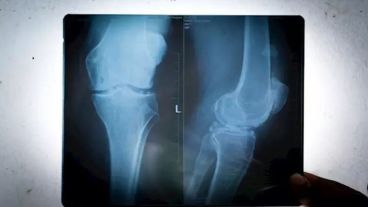

De 1918 a 2018 se triplicó el número de rodillas humanas que lucían fabelas, aparentemente inútiles, ya que son pequeños huesos enterrados en el tendón detrás de algunas rodillas, según publica el 'Journal of Anatomy' y reproduce Infosalus.

Para este nuevo estudio los científicos utilizaron 66 trabajos de investigación que abarcaban 27 países y 21.676 rodillas individuales. Esto incluyó estudios que identifican la fabela por rayos X y también por disección.